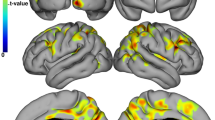

Of note, FreeSurfer failed in 9 PwMS and the median time between the MRI and neuropsychological examination was 2 months. The sample size in each table hereafter accounts for these failures. The comparisons regarding the cortical thickness between CI and CP PwMS are shown in Table 4. After correction for age, sex education, BDI-FS scores, WBV and thalamic volume, the CI PwMS had significantly thinner left fusiform gyrus (p = 0.0003, partial η [2] = 0.149), left inferior (p = 0.0032, partial η2 = 0.101), superior (p = 0.001, partial η2 = 0.128) and transverse temporal gyri (p = 0.0013, partial η2 = 0.119) and the right superior frontal (p = 0.002, partial η2 = 0.11) and superior temporal gyri (p = 0.0011, partial η2 = 0.121), when compared to the CP PwMS group (all surviving after Benjamini–Hochberg multiple comparison correction). (Table 4) No changes were noted after bootstrapping.

In an age, sex, education, BDI-FS, WBV and thalamic volume-adjusted logistic regression model, CI status was predicted using the thickness of the left fusiform (p = 0.001) and left cuneus gyri (p = 0.004). It successfully predicted CI in PwMS with 77.8% accuracy. The ROC curve predicting CI PwMS is also shown in Fig. 1. The area under the curve (AUC) was 0.863 (95% confidence intervals from 0.786 to 0.94).

ROC curve predicting cognitive impairment using demographic, clinical and neuroimaging measures. ROC receiver operating characteristic curve. The predictive measure utilized data from patient age, education, patient-reported depression (BDI-FS), whole brain volume, thalamic volume and thickness of the left fusiform and left cuneus gyr

After adjusting for age, sex, years of education, BDI-FS, WBV and thalamic volume, PwMS with isolated impairment in the cognitive processing speed had multiple significantly thinner cortical gyri including bilateral fusiform (p = 0.0002, partial η2 = 0.152 and p = 0.002, partial η2 = 0.11 for left and right respectively), bilateral inferior temporal gyrus (p = 0.0005, partial η2 = 0.138 and p = 0.014, partial η2 = 0.07), bilateral superior frontal/temporal gyri (p < 0.0091, smallest partial η2 = 0.08) and bilateral transverse temporal gyri (p = 0.0007 and p = 0.0076 for left and right, respectively, smallest partial η2 = 0.083).

A smaller number of cortical regions were significantly thinner in the PwMS with impairment in the language domain when compared to those without. After correction for age, sex, years of education, WBV and thalamic volume, the language-impaired PwMS had thinner left fusiform gyrus (p = 0.0032, partial η2 = 0.101), left pars opercularis (p = 0.0024, partial η2 = 0.107), left precentral (p = 0.0025, partial η2 = 0.106), left superior (p = 0.0019, partial η2 = 0.111) and transverse temporal gyri (p = 0.0008, partial η2 = 0.127) and the left insula (p = 0.0005, partial η2 = 0.135) as well as thinner right post-central gyrus (p = 0.045, partial η2 = 0.094) when compared to language-intact PwMS.

Additional linear regression analyses determined the best predictors of cognitive processing speed performance (as measured by SDMT scores) and verbal fluency performances (as measured by letter-based and categorical-based COWAT scores) after adjusting for age, sex, education, BDI-FS, WBV and thalamic volume. In addition to the significant effects from the WBV (standardized β = 0.31, p = 0.009), SDMT performance was significantly associated with left fusiform gyrus thickness (standardized β = 0.507 p < 0.001) with R2 increase from 0.214 to 0.294. Letter-based verbal fluency performance was significantly associated with WBV (standardized β = 0.312, p = 0.009), and left pars opercularis gyrus thickness (BA44) (standardized β = 0.438, p < 0.001) with R2 increase from 0.121 to 0.279. Similarly, categorical fluency performance was significantly associated with WBV (standardized β = 0.26, p = 0.036), and left pars opercularis gyrus (BA44) thickness (standardized β = 0.371, p = 0.001) with R2 increase from 0.094 to 0.204.

The findings of this study are multifold. As initially hypothesized, CI older PwMS had significantly thinner cortical gyri when compared to CP PwMS. In particular, the thickness of the fusiform gyrus and pars opercularis was associated with cognitive processing speed and verbal fluency performance. These findings were significant despite correcting for WBV and DGM-based measures.

Over a period of 5 years, a study by Eijlers et al. suggested that cognitive decline in older PMS is driven by significantly greater cortical atrophy [29]. In comparison, cognitive decline in the younger RRMS group was associated with lesion accrual rate whereas cognitive decline in the transitioning group (pwMS that transition from RRMS to PMS over follow-up) was associated with DGM atrophy [29]. Further, no differences were observed in DGM atrophy rates between the younger RRMS and older PMS groups [29]. As an extension to their work, we suggest that CI in older PwMS is driven by asymmetrically left-sided cortical pathology and localized to the fusiform gyrus, the inferior, transverse and superior temporal gyri. With the proposition that the cortical atrophy in long-standing MS may happen through a distinct and non-random pattern, a similar pattern of domain-specific cognitive impairments may follow suit [17].